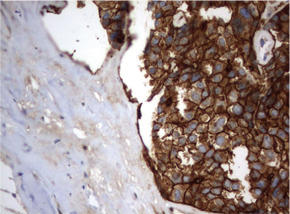

| 図.1 パラフィン包埋したヒト乳房組織の腺がんをanti-CD44 マウスモノクローナル抗体を使って免疫組織化学染色 左:UM500099 右:UM500098 |

| 図.2 パラフィン包埋したヒト結腸組織をanti-CD44 マウスモノクローナル抗体を使って免疫組織化学染色 左:UM500099 右:UM500098 |

| 図.3 パラフィン包埋したヒト肺組織をanti-CD44 マウスモノクローナル抗体を使って免疫組織化学染色 左:UM500099 右:UM500098 |

| 図.4 パラフィン包埋したヒト膵臓組織の細胞腫をanti-CD44 マウスモノクローナル抗体を使って免疫組織化学染色 左:UM500099 右:UM500098 |

| 図.5 パラフィン包埋したヒト甲状腺組織をanti-CD44 マウスモノクローナル抗体を使って免疫組織化学染色 左:UM500099 右:UM500098 |

| 図.6 パラフィン包埋したヒト前立腺組織の細胞腫をanti-CD44 マウスモノクローナル抗体を使って免疫組織化学染色 左:UM500099 右:UM500098 |